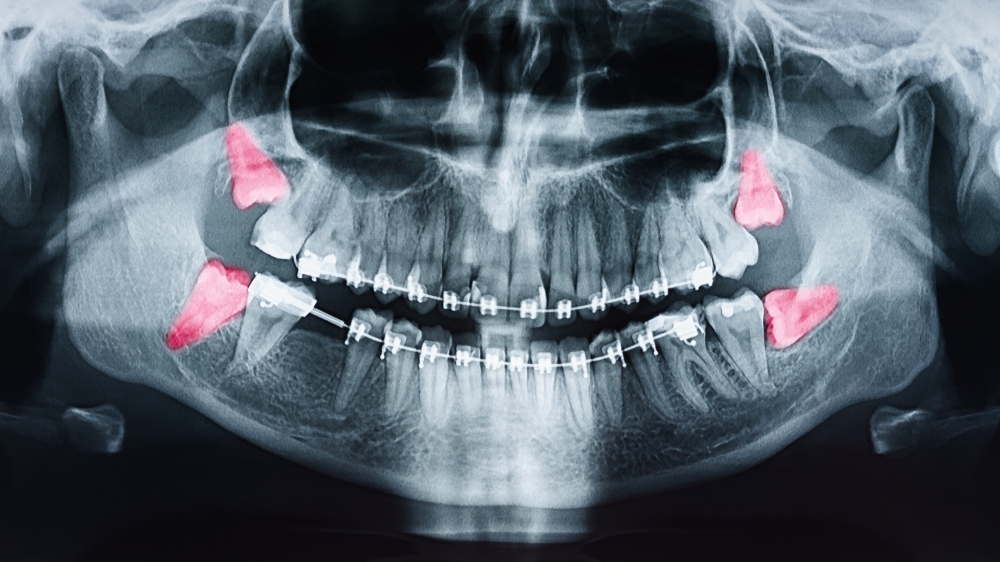

- Radiografia - zdjęcia rentgenowskie są niezwykle pomocne w diagnozowaniu chorób zębów i jamy ustnej. Pozwalają na wykrycie ubytków, stanu kości i korzeni zębów oraz innych zmian chorobowych.